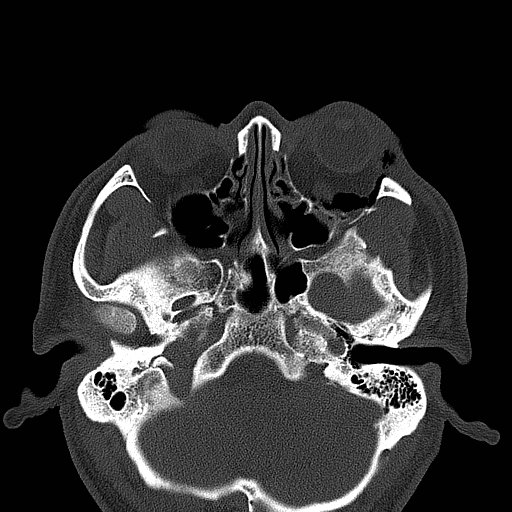

Physical exam showed marked left palpebral subcutaneous crepitus, as well as bulbar and palpebral conjunctival bulging. Visual acuity was normal with intact extraocular movements, and normal pupillary exam. Computed tomography (CT) imaging of the face was obtained and revealed multiple displaced fractures involving the left orbital floor and zygomatic arch associated with moderate periorbital and postseptal extraconal gas, resulting in orbital proptosis.